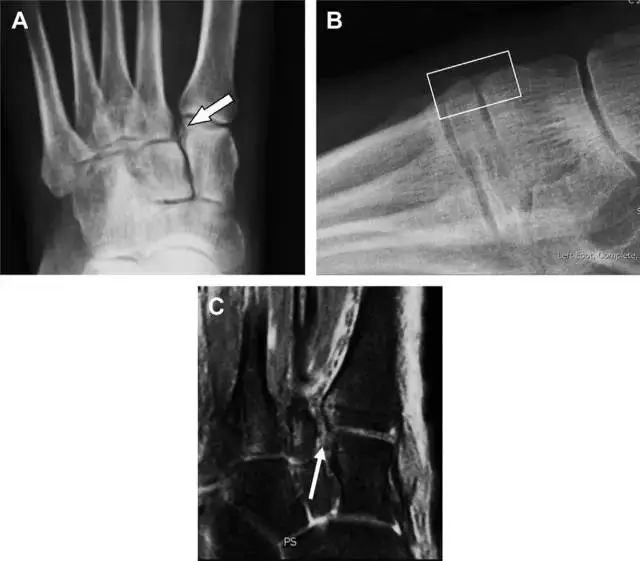

08前交叉韧带胫骨髁间嵴撕脱骨折

图 1 摩托车事故患者前交叉韧带撕脱性骨折

A 正位片示胫骨髁间嵴底部骨折(箭头),注意别把这个骨折碎片错认为关节内结构。B 侧位片示胫骨上方可见一细长型骨折碎片(椭圆)。C MRI 矢状位 T2 加权像示前交叉韧带附着于撕脱的骨折碎片上(箭头),注意周围存在骨髓水肿和积脂血征(空箭头)。